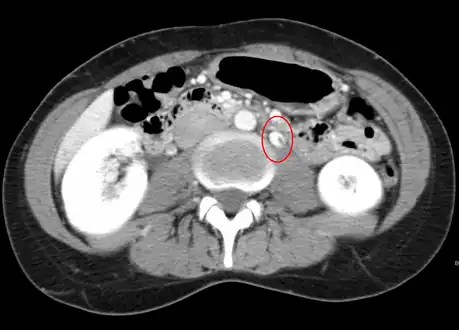

Left kidney with a suprarenal anechoic cyst-like lesion and hyperechoic intermedullary streaks in initial phase of renal vein thrombosis CT showing dilatation and thrombosis of the left renal vein in a patient with nutcracker syndrome

CT showing dilatation and thrombosis of the left renal vein in a patient with nutcracker syndrome